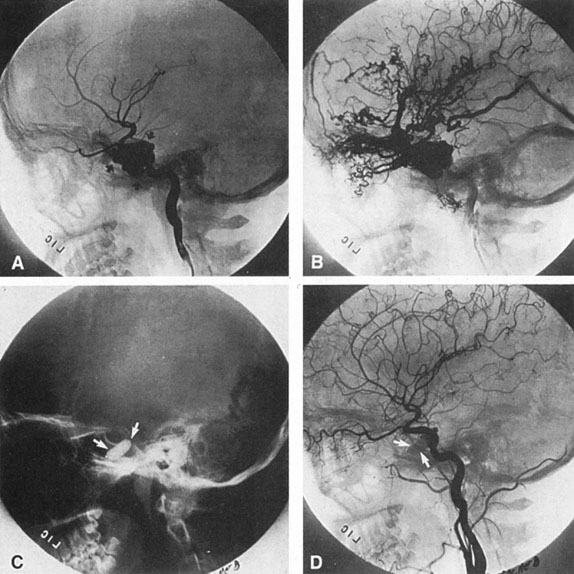

From 85% to 90% of AVMs are in the supratentorial compartment and are supplied primarily by the carotid circulation (Figs. 7 and 8). The remainder are supplied by the vertebrobasilar system. The approximate frequency of location is as follows: frontal, 22%; temporal, 18%; parietal, 27%; occipital, 5%; and deep intraventricular or paraventricular, 18%. The intracerebral site of the malformation does not necessarily indicate that there will be signs referable to that area simply from the mass effect of the malformation. Clinical features primarily result from subarachnoid hemorrhage or intraparenchymal hemorrhage with hematoma formation.

Fig. 7. Supratentorial arteriovenous malformation in a 28-year-old woman with a history of focal motor seizures for many years and a recent subarachnoid hemorrhage. A: Lateral projection carotid arteriogram demonstrating a huge deep hemispheral arteriovenous malformation. B: Frontal projection. C: Fundus photograph showing anomalous tortuous vasculature in each eye. No retinal arteriovenous shunt was detectable.

Fig. 8. Multiple supratentorial arteriovenous malformations (AVMs). A: Lateral projection of left carotid arteriogram shows dilated afferent artery (solid arrow) feeding the right hemispheric parietal AVM (open arrow). B: Right carotid injection fills a second, more posteriorly located, parietooccipital AVM (open arrow), which drains immediately to markedly dilated cortical veins (curved arrow).

In general, when hemorrhage occurs involving a portion of the visual radiations, a homonymous visual field defect is to be expected. Selective involvement of the anterior visual pathways may occur either with extensive venous angiomas at the base of the brain or as part of the Wyburn-Mason syndrome (see later), with direct involvement of the optic nerve, chiasm, or tract. Other variants such as congenital cavernous hemangiomas may involve the anterior visual pathways,68 as may intraparenchymal cryptic AVMs69 and present as symptomatic visual loss also resulting from hemorrhage and hematoma. Amaurosis fugax may even be the presenting symptom of supratentorial AVMs when blood is shunted to the meningeal circulation from the ophthalmic artery.70 When supratentorial AVMs drain into dural venous sinuses or the vein of Galen, distant ocular effects evolve, such as proptosis71 or ophthalmoplegia72 because of arterialization of cavernous sinus complex.

Of particular interest are those AVMs that involve the occipital lobe (Fig. 9). The clinical differentiation of migraine from a cerebral AVM was previously regarded as difficult because the clinical features of occipital lobe AVMs include visual phenomena or headaches. However, in most cases the clinical distinction is possible. In 26 cases with occipital AVM, two distinct syndromes were defined in 18 patients: occipital epilepsy and occipital apoplexy.73 Focal seizures with occipital malformations consist of elementary visual sensations similar to the phenomena evoked by direct cortical stimulations. When seizure activity occurs in the striate cortex (area 17), the patient usually reports sensations of moving lights in the right or left homonymous fields. The sensations are poorly formed, episodic, usually brief, sometimes colored, and unassociated with the angular, scintillating figures so characteristic of migrainous cortical phenomena. Epileptic discharges from areas 18 and 19 cause photopsias that are unlikely to remain stationary and to flicker rapidly. The epileptic photopsias usually last only seconds; occasionally they last for a few minutes before the onset of a generalized seizure. In other instances only the brief visual episodes occur without spreading to produce a generalized seizure. Momentary dimming or blindness in one or both homonymous fields may be experienced with seizure activity in the occipital areas.

Fig. 9. Carotid arteriogram of an occipital lobe arteriovenous malformation (AVM). Lateral (A) and frontal (B) projections demonstrating a small occipital AVM (arrow). The patient was a 23-year-old woman who presented with severe apoplectic unilateral headache, total left homonymous hemianopia, and mild nuchal rigidity. Despite xanthochromic cerebrospinal fluid, she was initially diagnosed elsewhere as having migraine. An AVM was successfully resected, and a small occipital lobe hematoma was removed.